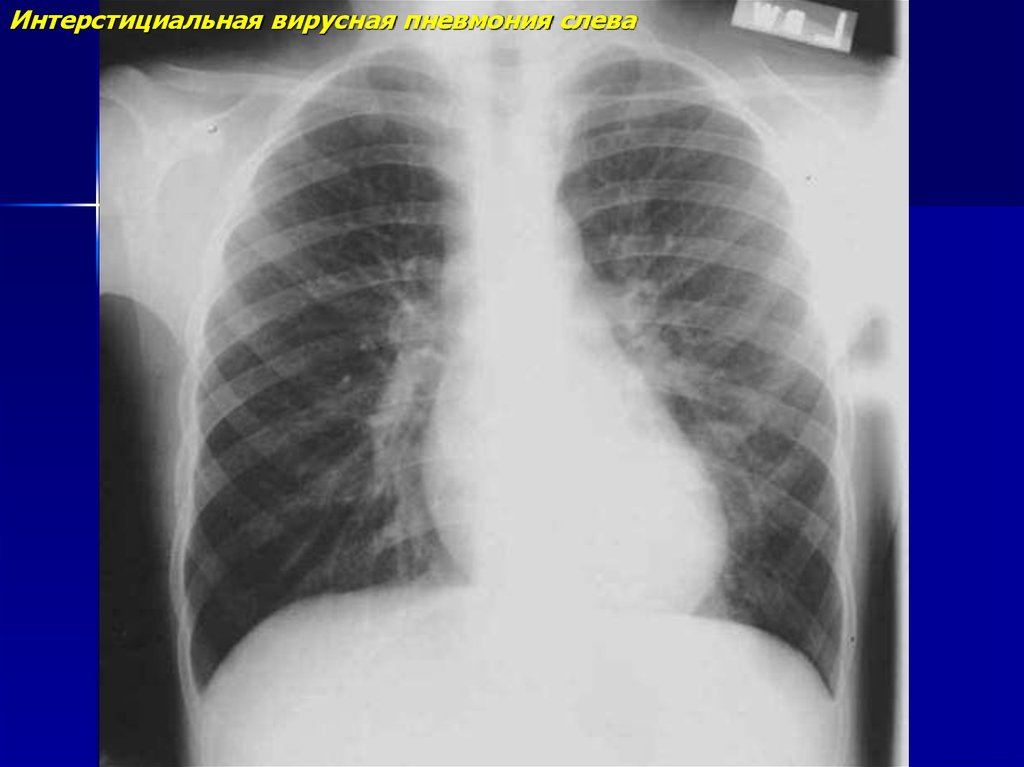

Интерстициальная вирусная пневмония слева